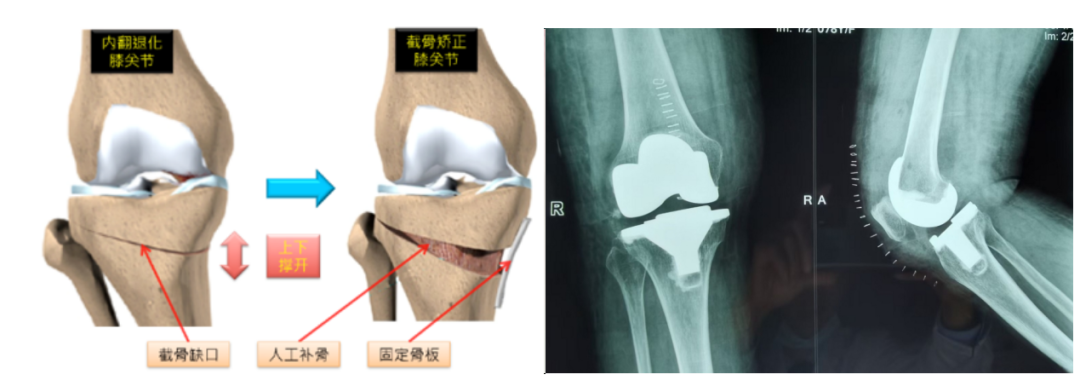

2、避免或显著推迟手术:积极早期管理可避免关节结构进一步恶化至需要关节置换的程度,或将手术需求推迟十年甚至更久。

忽视早期的代价是沉重的:当疾病进展到中晚期(软骨大面积磨损或剥脱、骨刺大量增生、关节严重变形),疼痛持续剧烈、关节活动度显著受限(无法伸直或弯曲)、跛行甚至影响睡眠。此时保守治疗往往杯水车薪,关节镜清理术效果有限且不持久,最终多数患者不得不面临创伤大、费用高、恢复期长的全膝关节置换术。